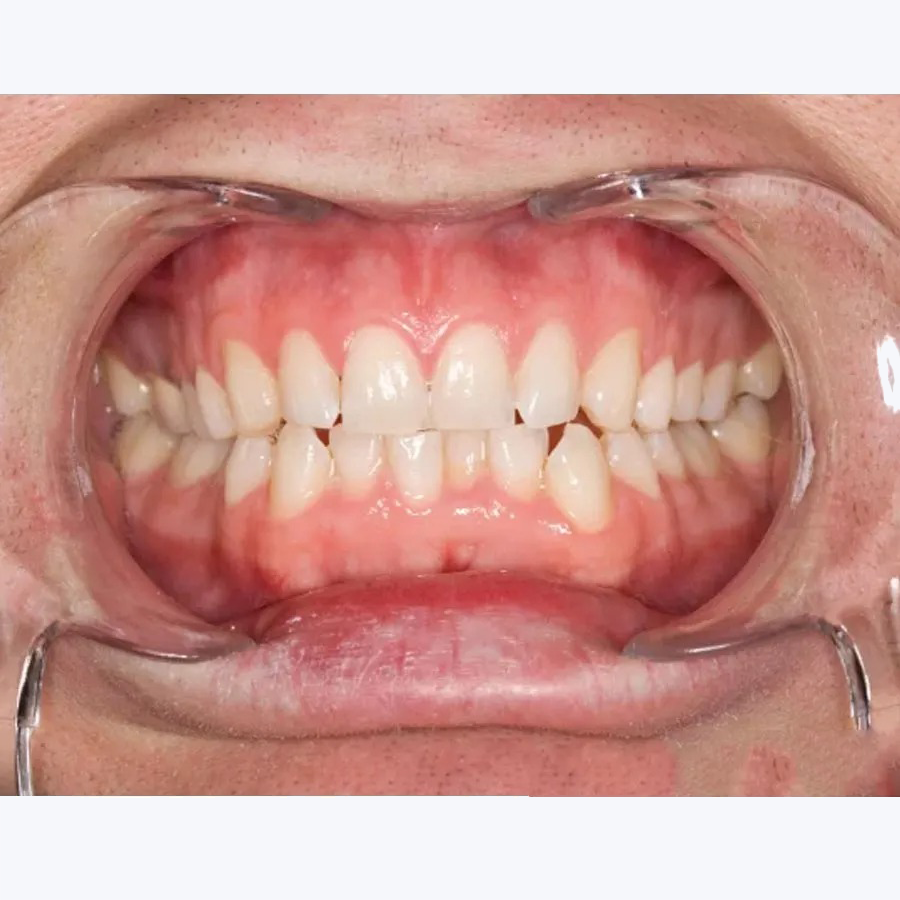

Surgery Hands Gloves